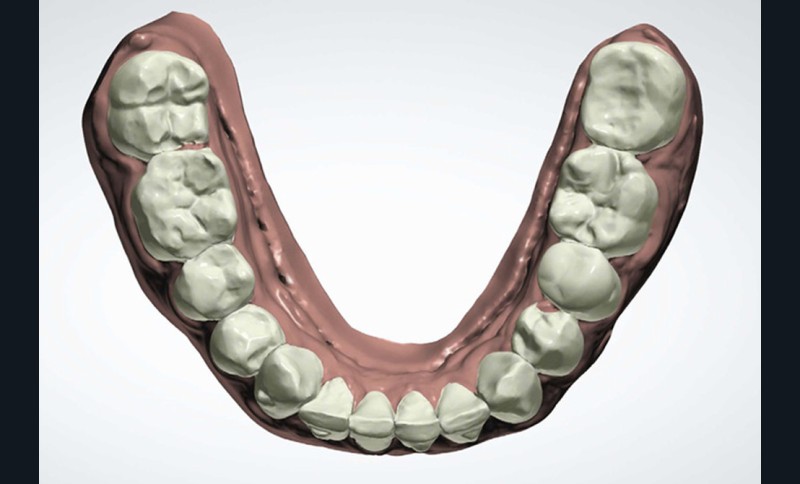

Présentation du cas clinique (fig. 1 à 3)

Le patient, âgé de 58 ans, présente un encombrement dentaire mandibulaire de 5 mm dans un contexte squelettique hypodivergent.